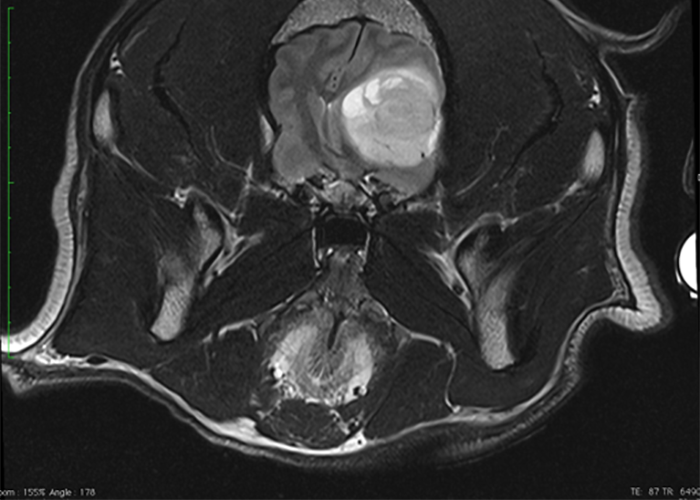

Depuis septembre 2020, notre centre est équipé d’une IRM Esaote Vet-MR Grande.

Cet outil diagnostic exceptionnel, innovant dans le milieu vétérinaire privé en Wallonie, permet de réaliser des examens non invasifs d’imagerie de pointe afin de réaliser des diagnostics pathologiques sur toute une série d’organe (cerveau, moelle épinière, articulations, cavités nasales, oreille interne, …). Cette machine a été installée dans un local exclusivement dédié à son utilisation et dont les paramètres de ventilation et de température ambiante sont parfaitement contrôlés. L’acquisition de cette IRM ouvre aussi la porte vers des chirurgies mieux préparées et plus pointues, dont la neurochirurgie (comme les hernies discales par exemple).